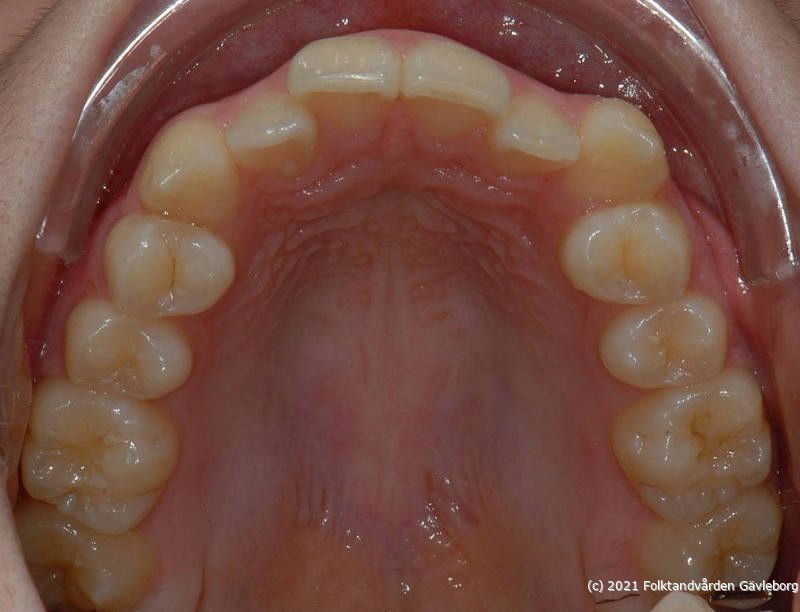

Specialisttandvård ortodonti

På ortodontiklinikerna diagnostiserar och behandlar vi bettfel på både barn och vuxna. Alla våra patienter kommer på remiss till oss. Vi behandlar bettfelen med fastsittande och avtagbar apparatur. Hos oss behandlas också de patienter som har avvikelser i käk- och ansiktsskelettet och som kräver tandreglering inför rekonstruktiv kirurgi. Vi har ett nära samarbete med allmäntandvård, privattandvård och övrig specialisttandvård i länet samt ett gott samarbete med Akademiska Sjukhuset i Uppsala när det gäller barn med olika syndrom och läpp-käk-gomdefekter. Våra specialistkliniker finns i Gävle och Hudiksvall.